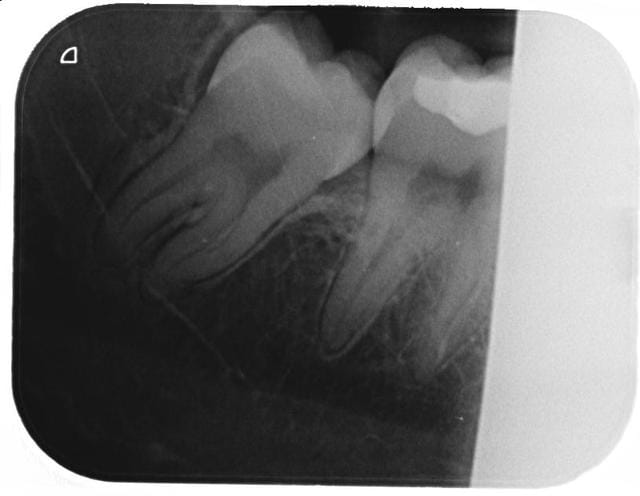

Je fais quoi? Pericoronite sur pericoronite.

Examen radio complementaire avant extraction?

48 op ex uguvk5 - Eugenol

Op ex2 iyntzw - Eugenol

paradoxe

30/07/2013 à 14h12

aterman écrivait:

-----------------

> Je fais quoi? Pericoronite sur pericoronite.

> Examen radio complementaire avant extraction?

Tu envois à mario180 pour lui faire plaisir;-)

Sinon un examen scan ou cone pour pouvoir préciser la position de la dent par rapport au nerf inf en 3D, bien sur.